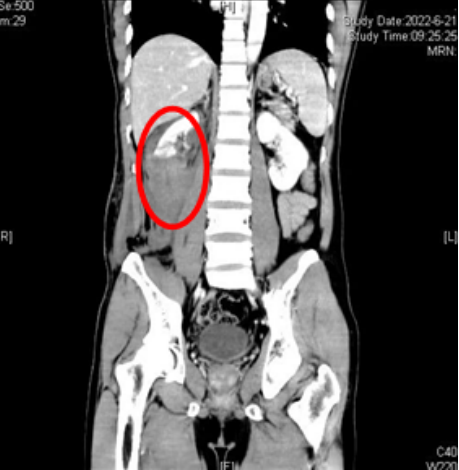

6月27日,家住长沙市天心区暮云的张明(化名)在翻修自建房的屋顶,由于天气炎热、身体疲乏,施工时不慎从三楼摔下,被120紧急送往香港马会app急诊科,入院后医生查体发现张明右侧背部、腰部大面积皮肤擦伤、皮下血肿,急诊CT发现右侧肾脏断裂,腹膜后巨大血肿形成。由于伤势非常严重,医院立即开辟绿色通道,泌尿外科迅速制定治疗方案,紧急采取手术治疗,最终切除右侧肾脏才使得患者脱离生命危险。

CT示患者右侧肾脏断裂、肾上极多处皮质裂伤,肾盂破裂,右肾周、腹腔及腹膜后多发积血